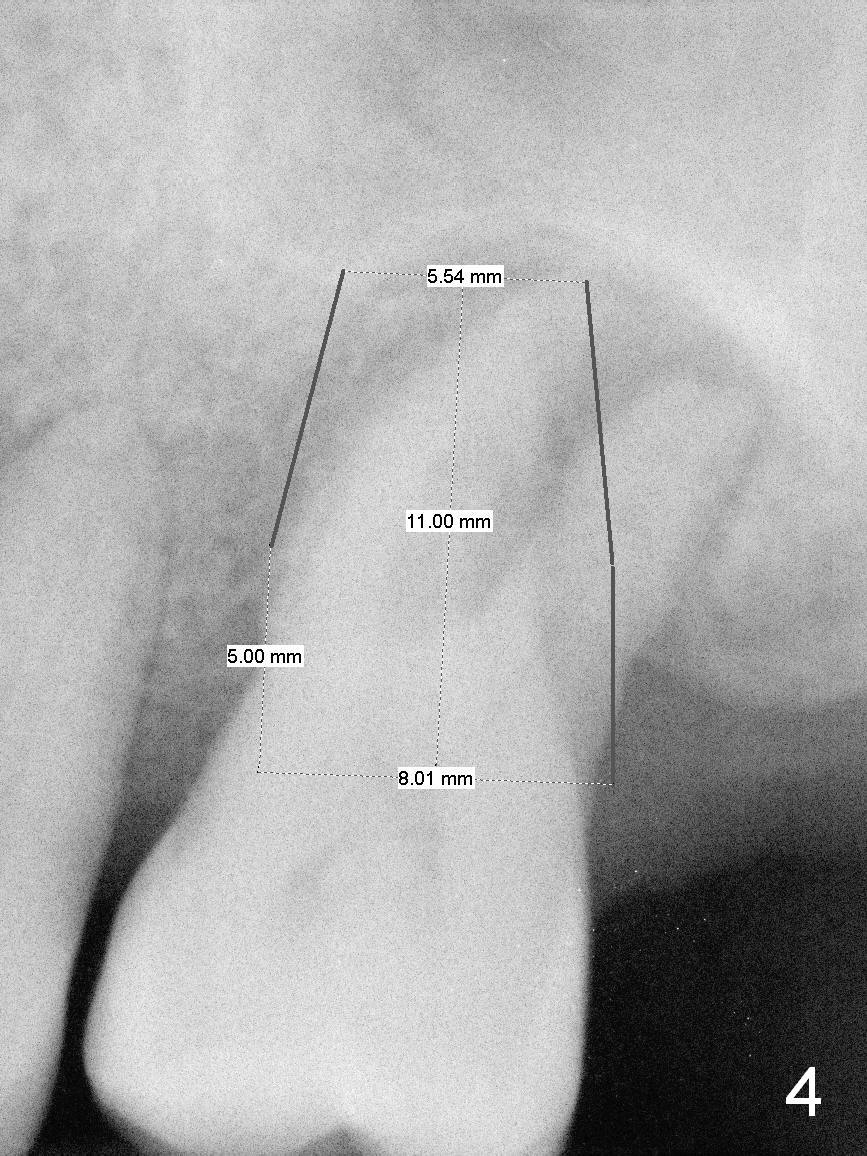

A large implant is place so that the mesiodistal dimension of the socket is obliterated by the implant (Fig.6 green circle). The buccal (Fib.5 B) and palatal gaps are filled with bone graft. It appears that either tapered (Fig4) or cylindrical (Fig.7) implant should be able to occupy the socket and obtain primary stability without perforating the sinus floor.